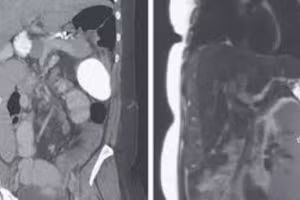

Phát hiện trường hợp lá lách “lang thang” hiếm gặp 27/11/2020 05:23 GD&TĐ - Một người phụ nữ bị đau bụng đến khoa cấp cứu và rất sốc khi biết được nguồn gốc dẫn đến cơn đau của mình. Đó là lá lách của cô di chuyển lệch khoảng 30 cm so với vị trí ban đầu.